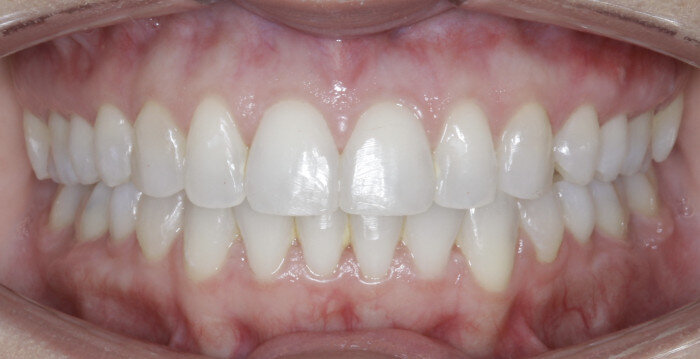

Once the intrusion has been completed, the TADs are tied to the wire and vertical elastics are used to close the bite without relapse of the intrusion. If buccal crown tip is seen, owing to the movement created by the intrusion, a power chain torquing sling is used to encourage lingual crown tipping and to prevent flaring of the incisors (Fig. 9). Once the case has been completed, the appliance is removed and a gingivectomy is performed to idealise the tissue shape and the final contours are made to the hard tissue (Figs. 10–12, end of treatment).